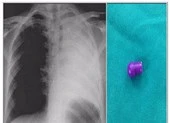

Sau khi thực hiện các xét nghiệm, bác sĩ (BS) chẩn đoán anh L. bị tắc ruột cơ học do dị vật nên chỉ định phẫu thuật lấy dị vật.

Trong quá trình phẫu thuật, các BS ghi nhận đoạn ruột hồi tràng xẹp, đoạn trên giãn lớn, viêm đỏ tía. Các BS kiểm tra và thấy dị vật gây tắc ruột hoàn toàn.

Sau khi mở ruột lấy dị vật, các BS xác định miếng nấm đông cô khá lớn có kích thước khoảng 5 cm còn nguyên.

Bác sĩ thăm hỏi sức khỏe anh L. sau khi phẫu thuật lấy nấm đông cô ra khỏi ruột. Ảnh: NGỌC DIỄM